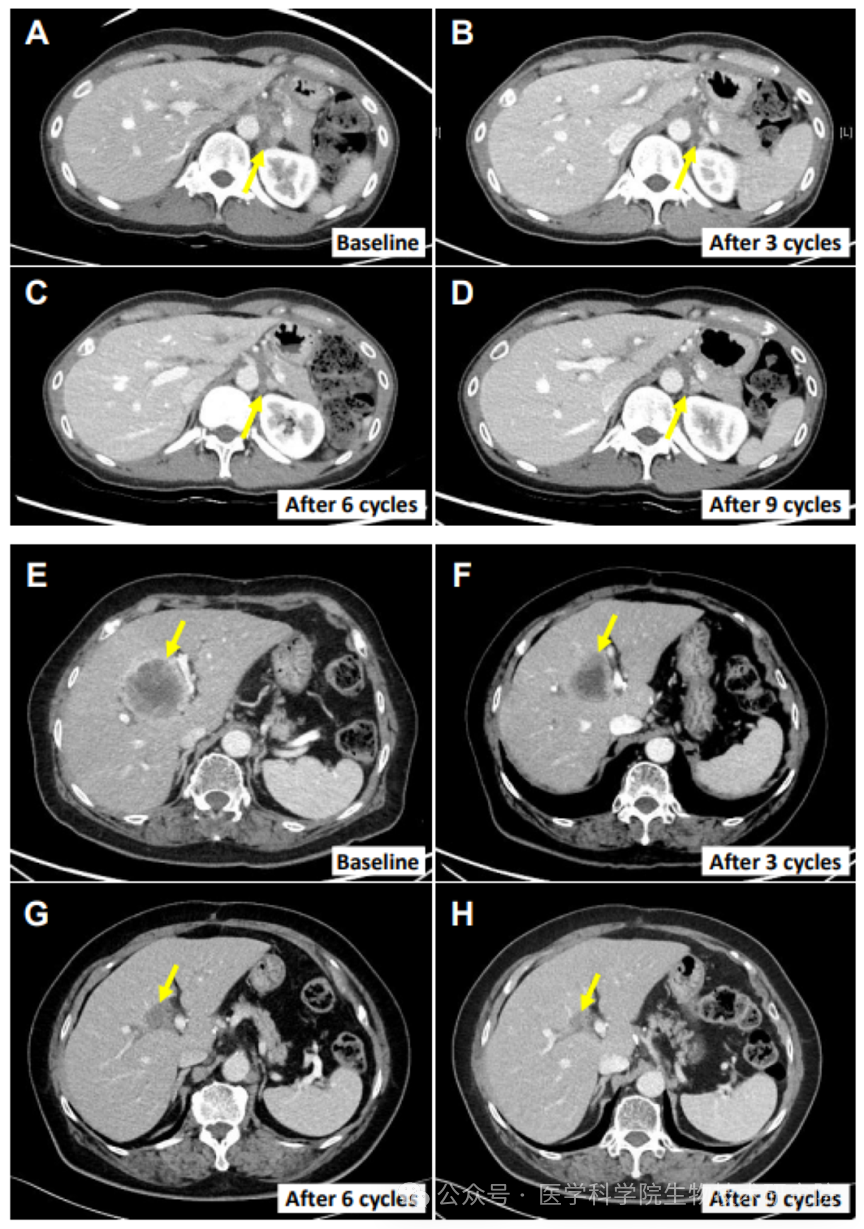

其中一名 40 岁女性患者的案例尤为典型:她确诊胆囊癌合并腹膜癌,经吉西他滨、顺铂等多种化疗无效后,接受该联合治疗,转移性淋巴结体积大幅缩小 82.3%,展现出双免疫联合方案的强大潜力。